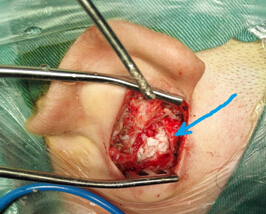

3.術(shù)前CT2 4.術(shù)中術(shù)腔中的巨大膽脂瘤